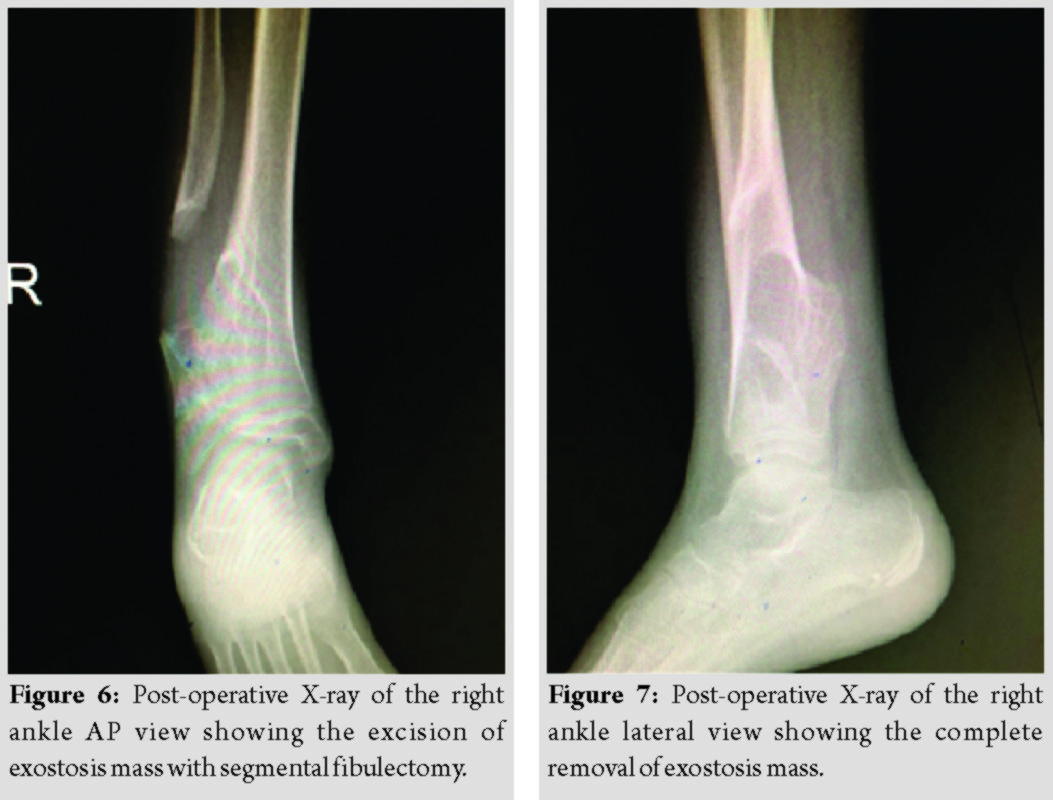

Post-operative period was uneventful and post-operative X-ray of the right ankle (Fig. 6, 7) showed complete removal of exostosis mass. The histopathology report was suggestive of osteochondroma (exostosis) with no malignant transformation and the patient was started on full weight-bearing after 3 weeks of surgery. At present (1 year follow-up), the patient has no pain and deformity (Fig. 8, 9) at the ankle and having good ankle range of motion. We are following up the patient regularly (till skeletal maturity) to check for ankle stability and deformity.